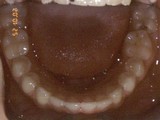

Zkřížený skus, předkus, nedostatek místa pro špičák. Léčba pomocí aparátu Hyrax a dále fixními aparáty v obou čelistech s jumping aparátem. V ústech přítomné MARA-stopy na dočasnou stabilizaci výsledku.

dolní pac2       dolní pac2